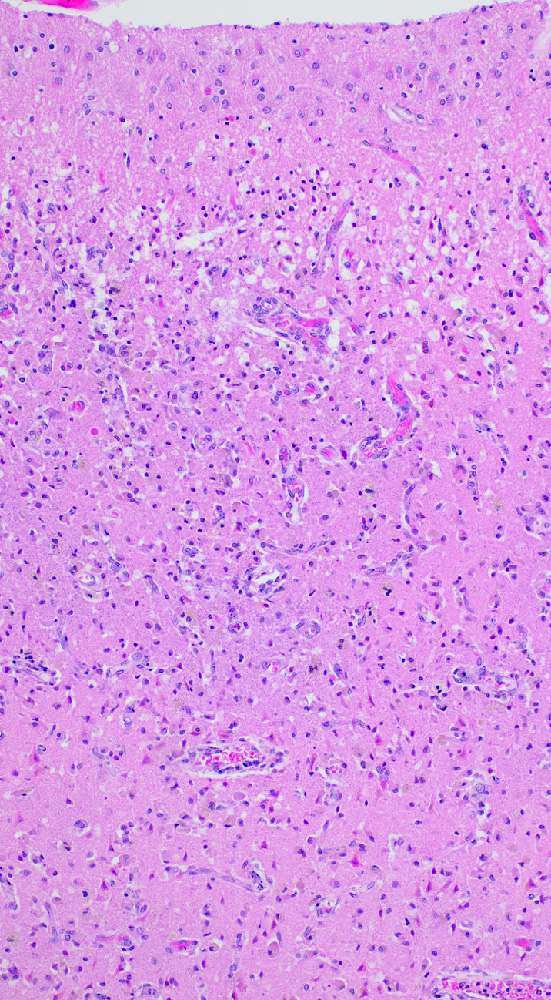

- Subacute (5 - 14 days)

- Dense macrophage infiltration and scattered siderophages

- Variable neutrophilic infiltration

- Peripheral reactive astrocytosis and microglial activation (i.e., rod shaped microglia)

- Hypereosinophilic neurons are still present in gray matter

- Neovascularization of necrotic tissue and reactive endothelial cells

- Chronic (15 days - years)

- Cavitated lesion with vessels and macrophages surrounded by a glial scar

- Reactive astrocytes in the edge of the cavitation

- Can be piloid gliosis with Rosenthal fibers, particularly in brainstem infarcts

- Scattered hemosiderin laden macrophages typically present

Microscopic (histologic) images